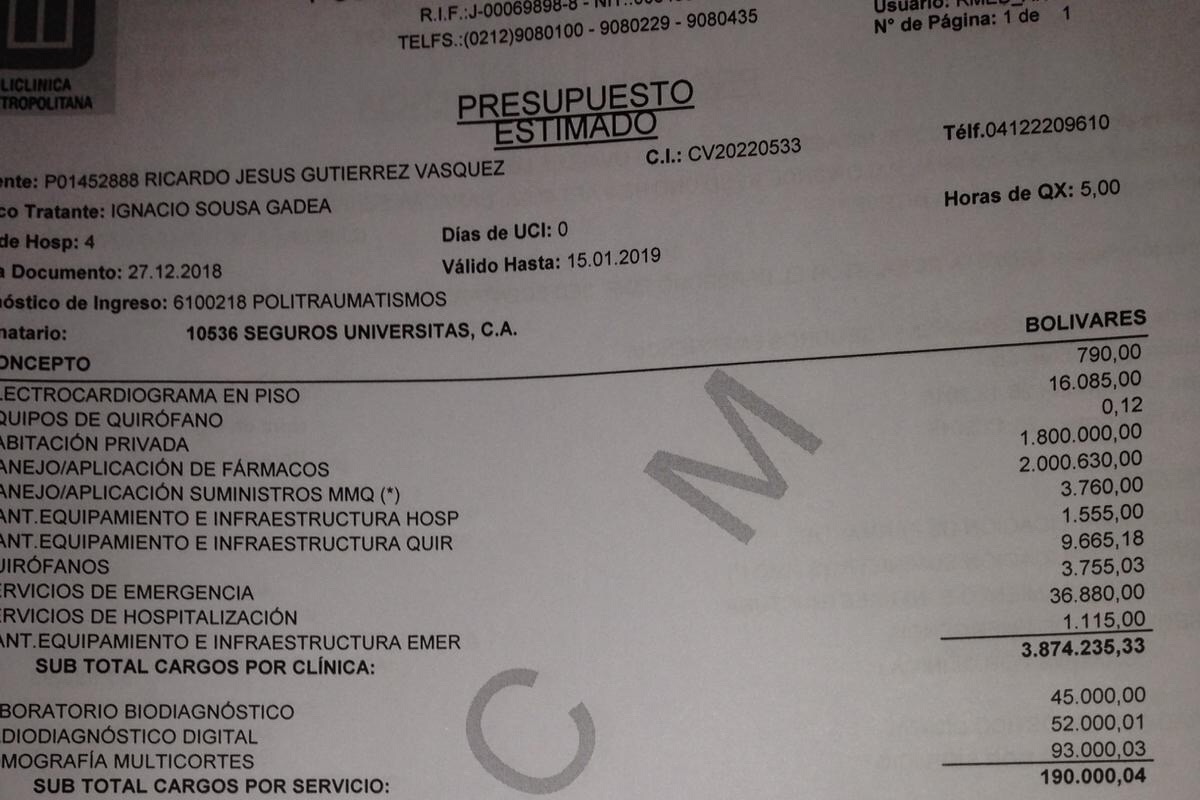

Los gastos de la clínica son 6.000$ mas 6.000$ de los honorarios profesionales del médico cirujano que lo operará, serán transferidos a una cuenta en los Estados Unidos de dicho médico cirujano o retirados y depositados en la misma.

Adjuntas las fotos del suceso, cuentas medicas, y otras documentaciones que respaldan el suceso.

Los gastos de la clínica son 6.000$ mas 6.000$ de los honorarios profesionales del médico cirujano que lo operará, serán transferidos a una cuenta en los Estados Unidos de dicho médico cirujano o retirados y depositados en la misma.

Adjuntas las fotos del suceso, cuentas medicas, y otras documentaciones que respaldan el suceso.